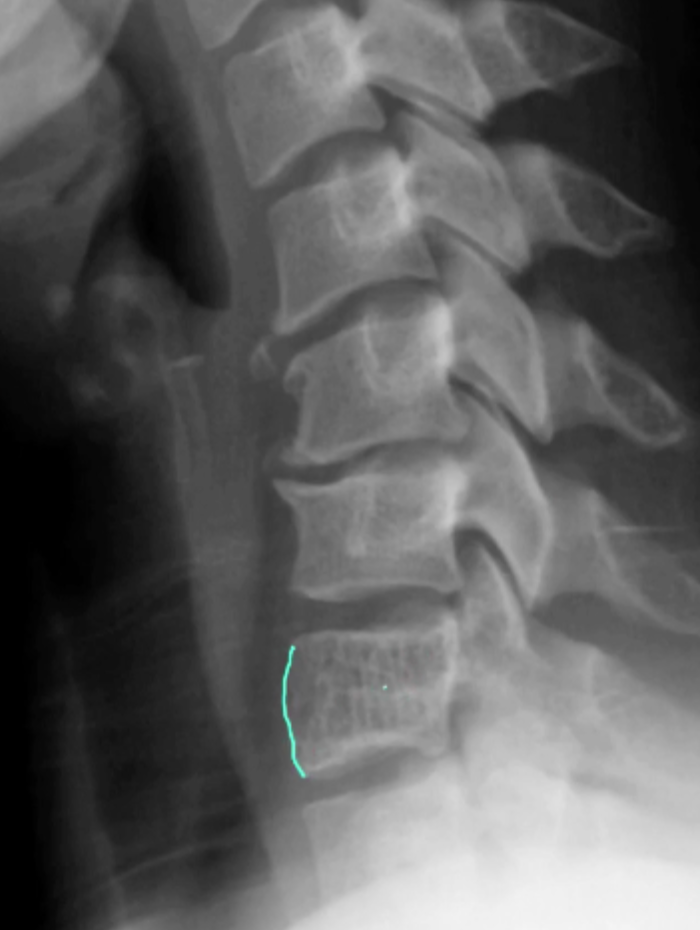

Segond fracture

Dr Subhan Iqbal◉ and Assoc Prof Frank Gaillard◉◈ et al.

Segond fracture is an avulsion fracture of the knee that involves the lateral aspect of the tibial plateau and is very frequently (~75% of cases) associated with disruption of the anterior cruciate ligament (ACL). On the frontal knee radiograph, it may be referred to as the lateral capsular sign.

The classical appearance of a Segond fracture is that of a curvilinear or elliptic bone fragment projected parallel to the lateral aspect of the tibial plateau. This has been referred to as the lateral capsular sign 1, which is best seen on the anteroposterior view of the knee.